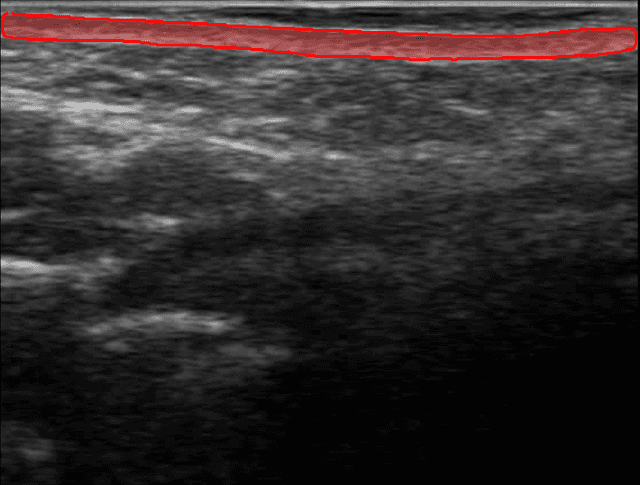

Seguimiento Visual del Progreso

Sigue mejoras medibles a lo largo de las sesiones de tratamiento. Visualiza cambios en la calidad de la dermis con comparaciones precisas de antes y después.